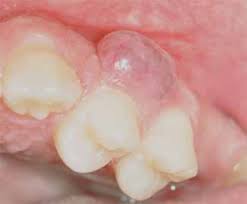

Peripheral ameloblastoma mostly appears in the alveolar mucosa.

• It is a soft-tissue version of an ameloblastoma but can also involve the underlying bone.

UnknownNatlJMaxillofacSurg_2013_4_2_245_127662_f2